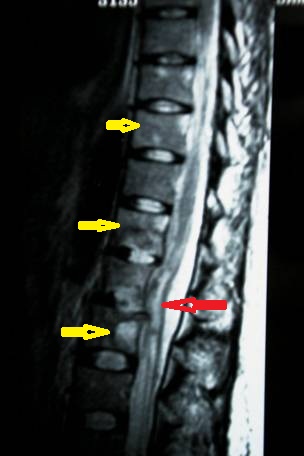

- Figura No 4a

- Figura No 4b

- Figura No 4c

- Figura 4 Texto